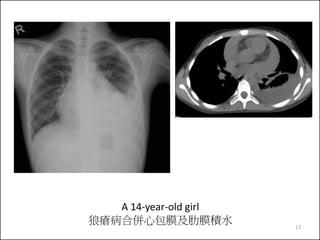

A 14-year-old girl

狼瘡病合併心包膜及肋膜積水